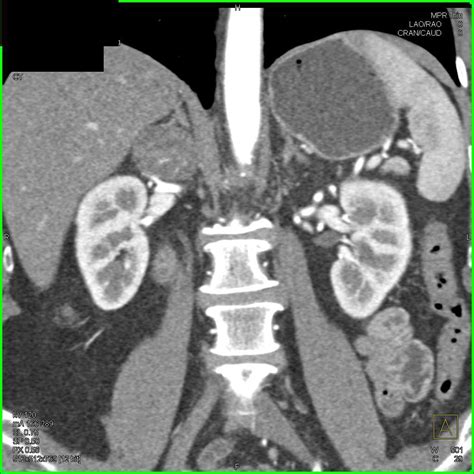

An Adrenal CT Scan, or Computed Tomography, is a non-invasive diagnostic imaging procedure that uses advanced X-ray equipment combined with computer processing to create detailed, cross-sectional images of your adrenal glands. Unlike a standard X-ray, which provides a two-dimensional view, a CT scan provides a comprehensive three-dimensional perspective, allowing radiologists to identify even the smallest nodules, tumors, or signs of inflammation.

This imaging modality is highly sensitive and is considered the gold standard for evaluating adrenal masses. Whether your doctor suspects adrenocortical carcinoma, pheochromocytoma, or adrenal adenomas, this scan provides the structural data necessary to determine the size, shape, and density of the tissues in question.

Once the Adrenal CT Scan is complete, the images are sent to a radiologist. They analyze the "attenuation" or density of any detected masses. This is measured in Hounsfield units (HU). A low density (measured in low HU) typically suggests that a mass is a benign adenoma, which is very common. Conversely, higher density or irregular borders might prompt the medical team to conduct further investigations, such as follow-up blood work or specialized biopsies.